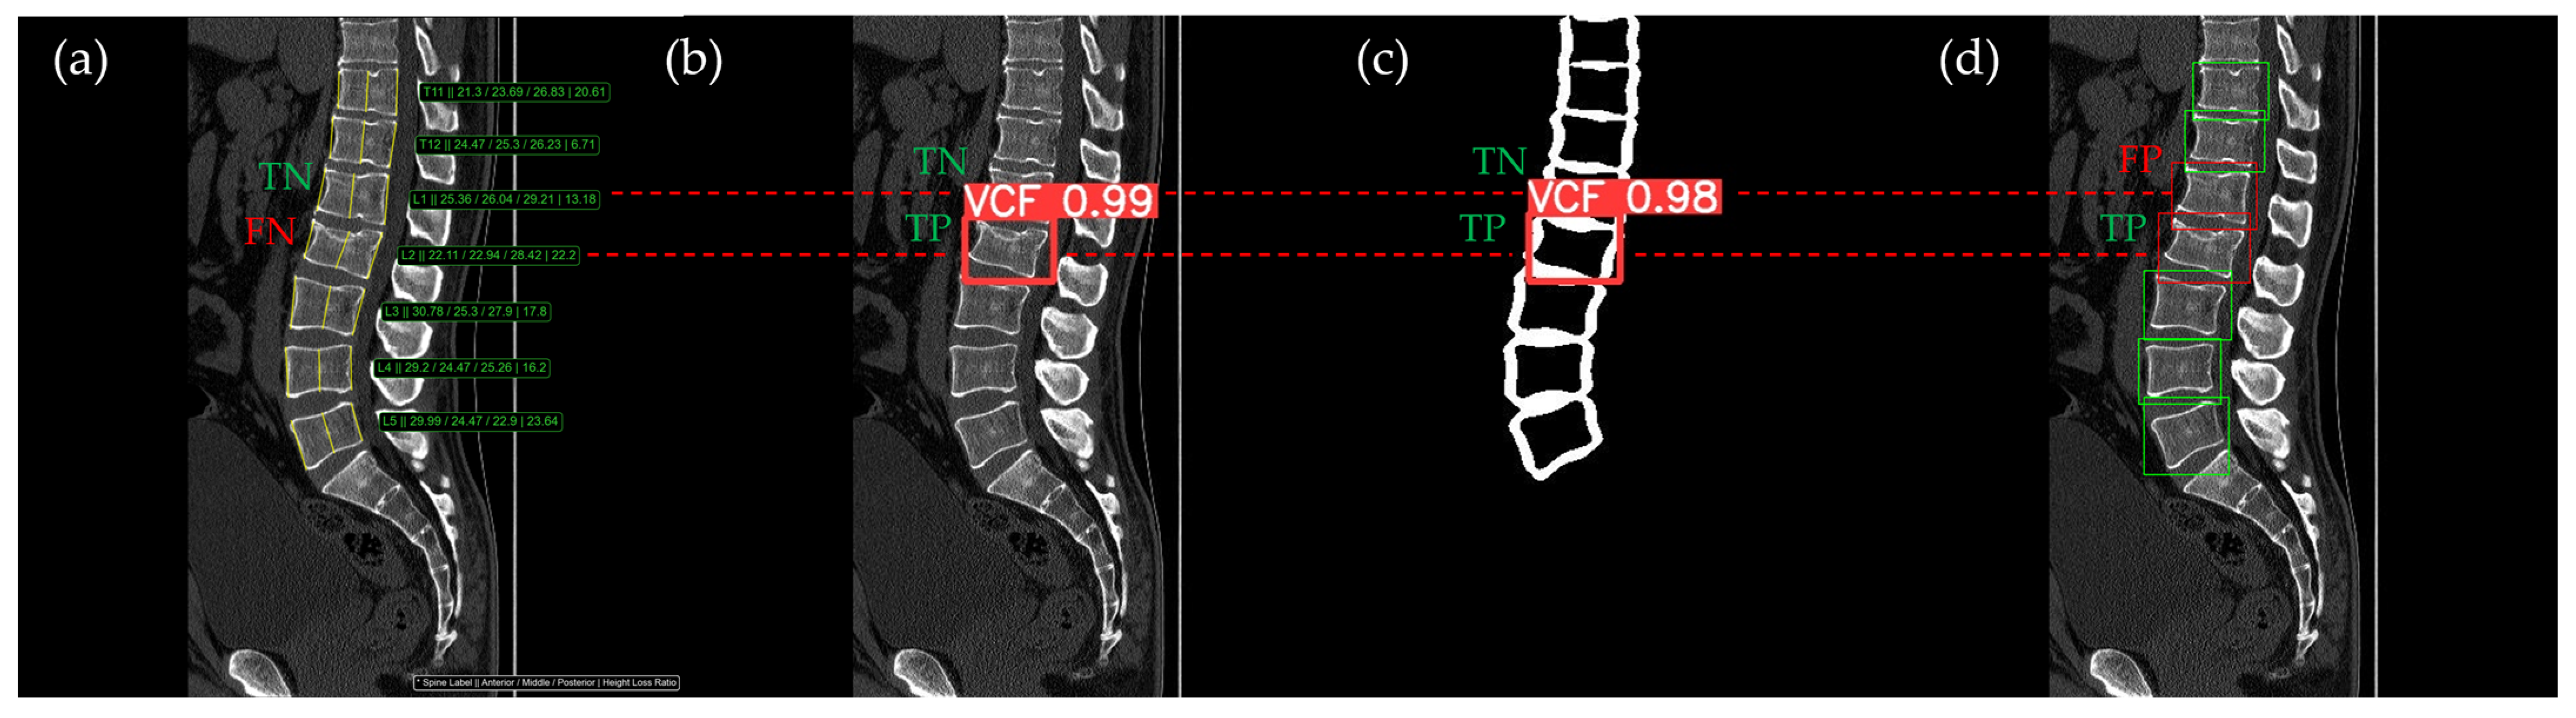

Figure 10, Figure 11, Figure 12, Figure 13 and Figure 14 illustrate typical examples of results for HLR, EEVD, TSVD_SD, and TSVD_DC in patients with acute VCFs. The results of applying different methodologies to the same patient image and identical slice locations were as follows. In the HLR results, each vertebra was marked with yellow solid lines indicating the height measurement lines for the anterior, middle, and posterior regions. The measured height values and HLR percentages were displayed on the right side of the image. If the HLR percentage ranged between 25% and 40%, it was highlighted in orange, while values of 40% or higher were highlighted in red. In the EEVD results, the VCF detection outputs were displayed along with their respective confidence scores based on the input patient images. For the TSVD_SD results, after performing spine segmentation, the model extracted only the spine contour, and the VCF detection results with their corresponding confidence scores were presented. In the TSVD_DC results, bounding boxes were generated for each vertebral body, with normal vertebrae represented in green and vertebrae identified as VCFs displayed in red.

In Figure 11, the acute VCF was also present only at the L2 level, with minimal height loss but evidence of cortical breakage at the anterior upper region. In the HLR method, the result was an FN, while EEVD, TSVD_SD, and TSVD_DC correctly detected it as a TP. In addition, HLR produced FP at the T11 and T12 levels. The T11 vertebra was potentially misinterpreted as a VCF due to its wedge-like deformation; however, the radiological assessment concluded it was normal. Both T11 and T12 were classified as VCFs by HLR based on height measurements exceeding 25% and were classified as moderate VCFs according to the Genant classification.

Figure 11. The VCF detection results from four different methods. (a) HLR, (b) EEVD, (c) TSVD_SD, and (d) TSVD_DC. The acute VCF, as confirmed by the radiologist, was only located at the L2 level. TP, TN, FP, and FN were marked at the same level with a red dotted line. FP occurred at the thoracic vertebrae only with the HLR.